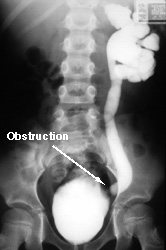

You order the voiding cystourethrogram (VCUG) seen at the right. Notice that there is no contrast in the right ureter or kidney. Contrast enters the left kidney by traveling up the ureter from the bladder (reflux). Although reflux is present, the distal ureter is obstructed causing hydronephrosis and enlargement of the ureter. Most megaureters don't have reflux.

The obstruction is caused by deficiency of muscle at the distal ureter. The lumen of the ureter is normal, but a peristaltic wave, generated in the renal pelvis, is blocked near the bladder preventing effective conduction of urine into the bladder.

Unlike some other obstructions to the flow of urine, megaureters typically have no physical narrowing of the lumen. Rather, they have a defect in the conduction of a muscle contraction at the distal end of the ureter. This results in urine flowing through this point at a slowed rate. This causes hydronephrosis in the kidney and ureterectasis (widening of the ureter) in the upper ureter.